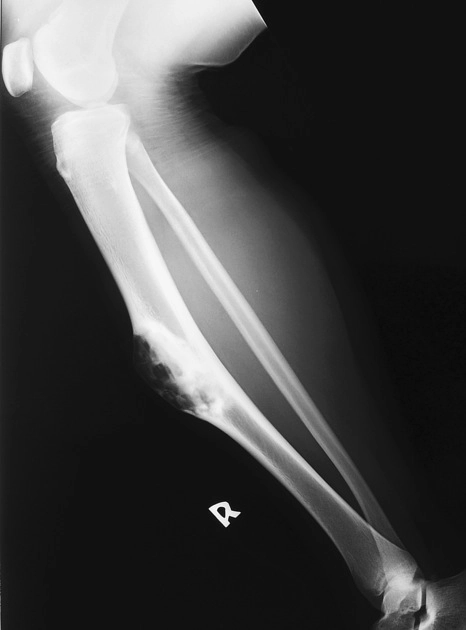

Loạn sản xơ xương (Fibrous dysplasia - FD)

Loạn sản xơ tạo xương (Osteofibrous dysplasia)

U xơ tạo xương (Ossifying fibroma)

U xơ không cốt hóa (Non-ossifying fibroma - NOF)